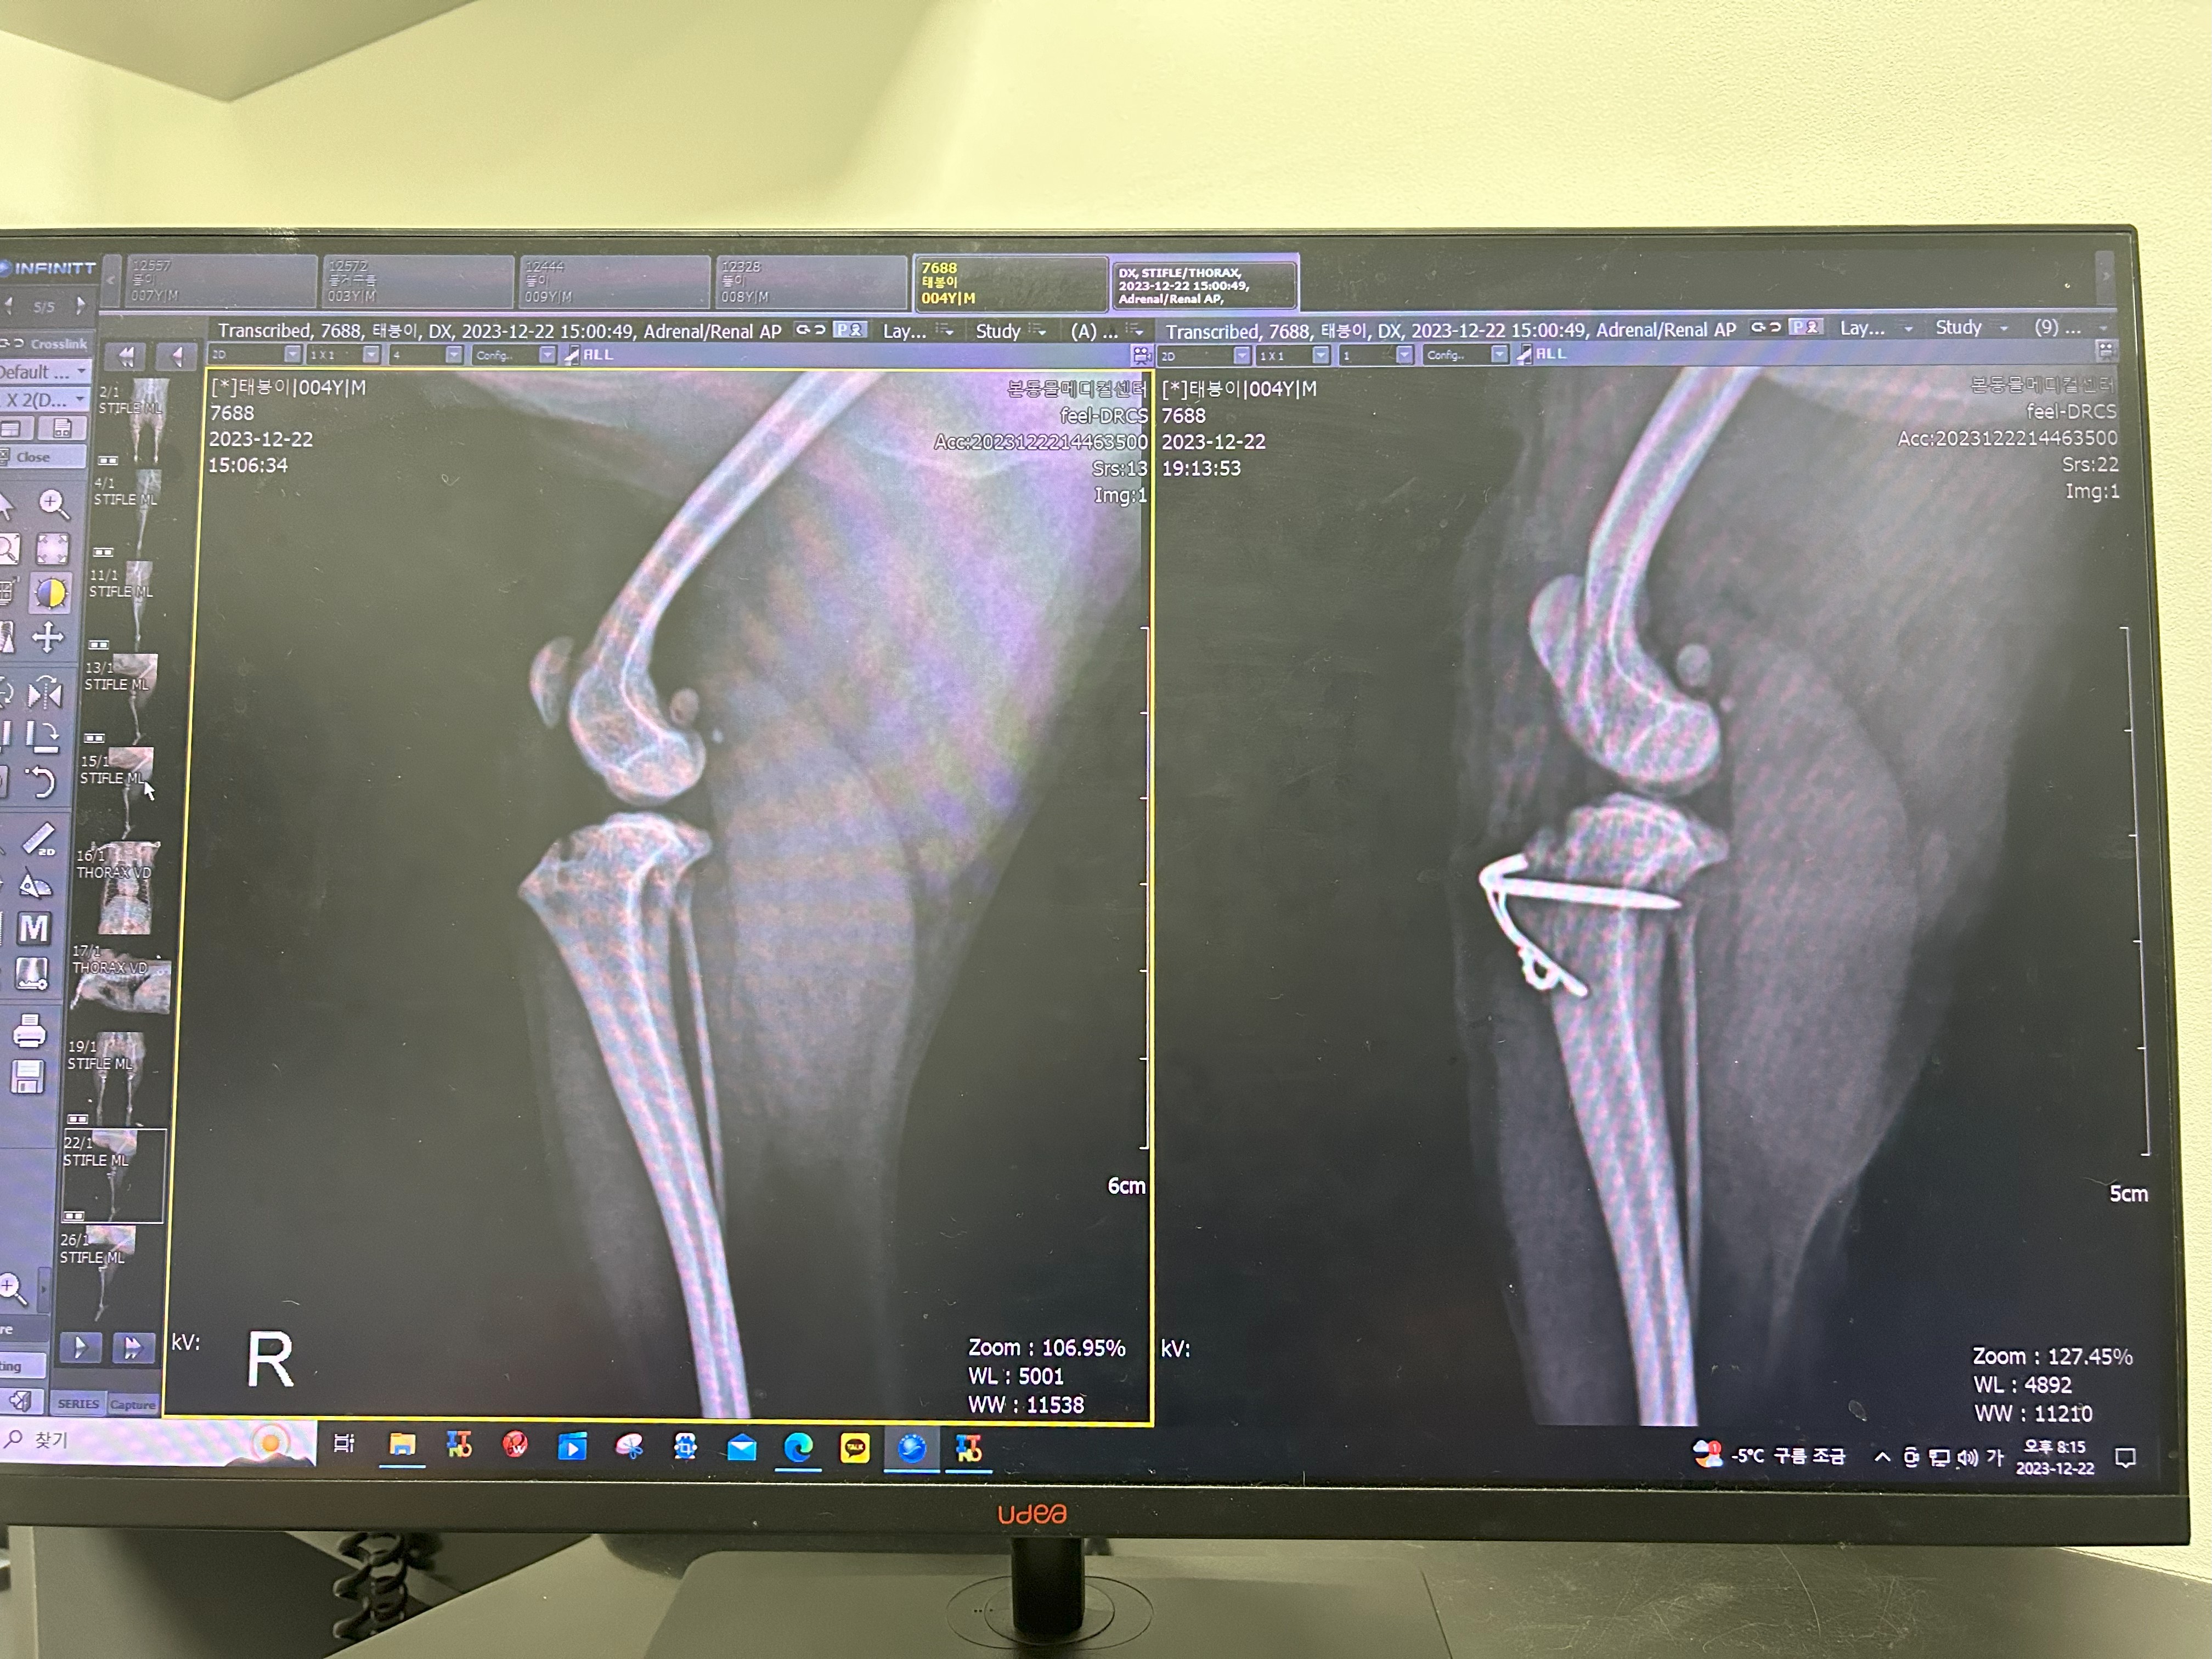

저녁타임에 수술을 하게 돼서 수술 전에 하는 혈액검사와 엑스레이 검사 등을 하고

슬개골탈구 수술

태봉이가 하게 된 강아지 슬개골탈구 수술은 세 가지를 한다고 했어요

제가 전문적인 용어는 잘 몰라서 저의 수준으로 설명을 하자면

소형견들은 무릎뼈를 받쳐주는 뼈의 골이 매우 얕거나 거의 평평해서 경우에 따라 슬개골이 빠지는 경우가 많은데

그 뼈의 홈을 깎아내서 인의적으로 골을 내줘야 합니다.

그래서 그 홈을 깎아내는 수술을 해야 하고

거기에 슬개골이 빠지면서 제자리에 위치하지 못한 슬개골을 제자리에 위치하게 하는 수술,

그리고 와이어로 슬개골을 고정하는 것까지 이렇게 세 가지를 진행했어요